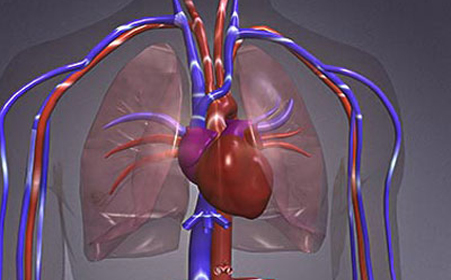

寒冬如何护心_康益膏方